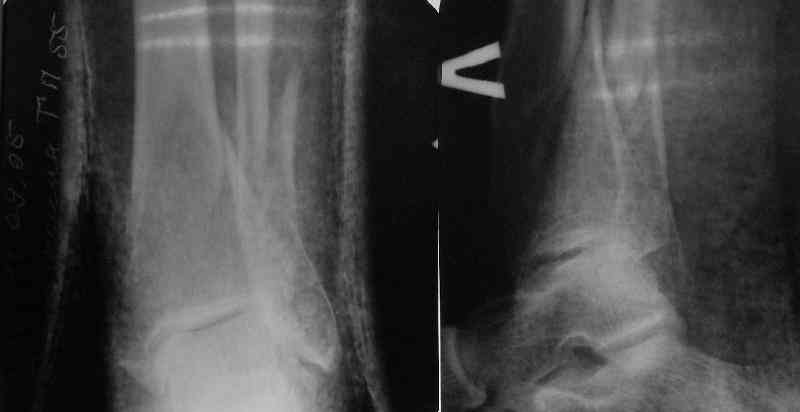

A typical case is attached, also an image with intra-op reduction obtained by a small wire distractor, in the moment of insertion a Poller wire in AP direction. Fixation by a SIGN nail. Despite the fibula was not fixed healing was obtained with the unchanged alignment.

Very interesting application, but is the final position in a little distal varus with some fibula

distraction? Would that have been eliminated by fibula plating?

TDVC> Very interesting application, but is the final position in a

TDVC> little distal varus with some fibula distraction?

At least both the ankle mortise and tibial alignment look acceptable, don't they?

TDVC> Would that have been eliminated by fibula plating?

I am just trying to illustrate that prevention of 1)tibial valgus and 2)loss of reduction can be provided without fibular plating. Small changes of conventional nailing techniques allow to maintain reduction of the tibia reliably without adjunctive fibular stabilization.

In delayed cases acute length restoration performed only in the tibia may leave the fibula shortened thus change the mortise. So it is reasonable to restore length of both bones simultaneously by distractor and fix the fibula not with open reduction and plating but just by a single perQ screw. Example attached.